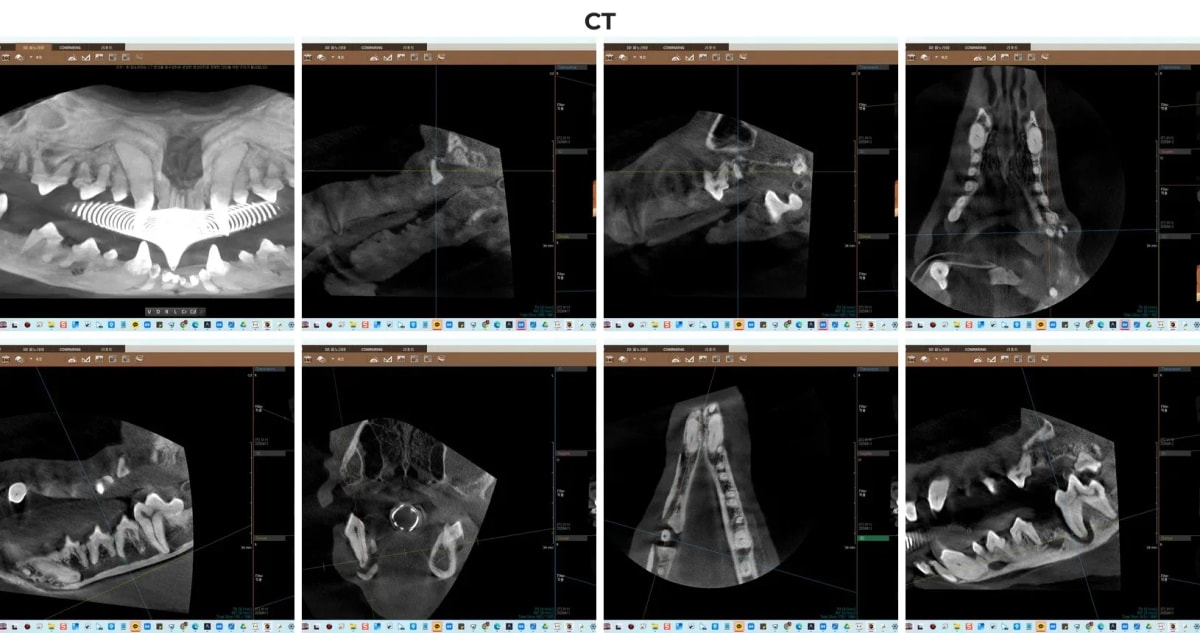

2. 턱뼈 골절 예방을 위한 필수 과정: 치과 전용 CT 진단

ℹ️ 치과 CT의 중요성

하루처럼 하악 뼈 소실이 심각한 경우, 2차원 일반 엑스레이만으로는 남아있는 뼈의 입체적인 두께와 신경관의 정확한 위치를 파악하기 어렵습니다. 광주 전남 유일 치과 CT를 보유한 본원에서는, 3D 영상 분석을 통해 턱뼈의 가장 얇은 지점을 밀리미터(mm) 단위로 측정하고, 1년 전 다른 병원에서 발치하다 남겨둔 잔존치근(부러진 치아 뿌리)의 정확한 깊이까지 정밀하게 찾아낼 수 있었습니다.

광주 전남 유일 치과 CT를 통한 하루의 3D 턱뼈 및 치근단 정밀 분석 영상